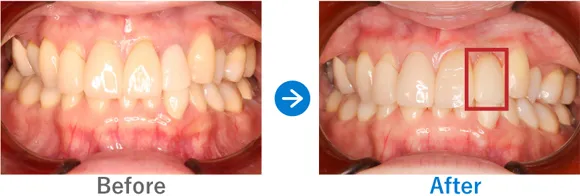

Case9

約30年間ぐらぐらしていた前歯をインプラントに。即時に仮歯が入り仕上がりにも納得

右上前歯のぐらつき

インプラント1本:右上1

347,000円(内訳:抜歯即時埋入、インプラント1本(ノーベル)、仮歯、保証5年)

来院の背景

19歳のときに転んだはずみで前歯がぐらつくようになり、これまで他院での治療でなんとか維持してきましたが、ここ最近で急にぐらぐらするようになってきたそうです。ご自身の感覚では歯の根元がダメになっている気がするので、早くなんとかしてほしいと来院されました。

治療結果

前歯がダメージを受けてから30年近く経っているため、骨吸収が進んで歯が長くなっている状態でした。一方で、歯の根っこの先には異常がないことを確認できたため、前歯ということもあり早めに治療をスタート。抜歯後にすぐ仮歯を入れる方法で治療を進めました。

骨吸収が進んでいたため歯は長めになりましたが、事前に説明していたこともありご納得いただける結果となりました。